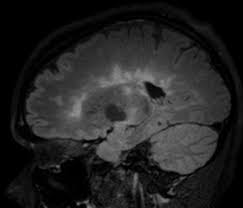

التصلب اللويحي في الدماغ - العلاج في أوكرانيا علاج التصلب اللويحي باستخدام الخلايا الجذعية / الجهاز العصبي المركزي • يصيب كل من الكبار والصغار • مرض مزمن يصيب جزء من الدماغ المسمى غشاء المايلين أو النخاعين أو المسماة بالمادة البيضاء في الجهاز العصبي • يصيب النساء اكثر من الرجال.. في مرض التصلب اللويحي (العصبي المتعدد) يكون هناك التهاب في غمد الميالين أو غطاء الألياف العصبية في الدماغ والحبل الشوكي حيث يتسبب هذا الالتهاب في تلف الميالين ولا يمكن للإشارات العصبية أن تنتقل على طول الألياف العصبية. التصلب المتعدد ويعرف بأسماء عديدة، منها التصلّب اللويحي والتصلب المنتثر أو التهاب الدماغ والنخاع المنتثر (بالإنجليزية: التصلب اللويحي ؟ التهاب المادة البيضاء ؟ multiple sclerosis ؟. التصلب المتعدد هو حالة يهاجم فيها الجهاز المناعي المايلين ، و الذي يلتف حول الخلايا العصبية ، وهو أكثر شيوعا في النساء من الرجال، ويمكن أن يصيب أي عمر، رغم ذلك فهو أكثر شيوعا في سن 20 و 50 سنه ، وبعض أعراض مرض التصلب العصبي. التصلّب اللويحي المتعدد هو مرض مناعة ذاتية ليس له علاج حتى الآن.

في مرض التصلب اللويحي (العصبي المتعدد) يكون هناك التهاب في غمد الميالين أو غطاء الألياف العصبية في الدماغ والحبل الشوكي حيث يتسبب هذا الالتهاب في تلف الميالين ولا يمكن للإشارات العصبية أن تنتقل على طول الألياف العصبية.

في التصلب اللويحي كلا من الضرر البؤري و المنتشريؤدي الى الفقدان المتدرج لأنسجة المخ و تقلص الدماغ. يستخدم أيضاً في حالات عمليات زراعة الأعضاء. عدد الإنتكاسات التي يصاب بها المرض 2. سرطان الدماغ نمو غير طبيعي للخلايا في الدماغ. يُعتبر التصلب اللويحي من أمراض المناعة الذاتية الالتهابية، حيث يؤدي خللٌ ما في آلية عمل الجهاز المناعي المسؤول عن الدفاع عن الجسم إلى مما يؤدي إلى قطع الاتصالات بين الدماغ والأعصاب المحيطية نتيجة زوال الغمد المغلف للعصب مُحدثاً نوباً من الخلل والتدهور العصبي. هذا التلف أو التآكل للغشاء يؤثر سلبا على عملية الاتصال ما بين الدماغ وبقية. هنالك 4 مفاتيح لقياس نشاط التصلب اللويحي: التصلب المتعدد ويعرف بأسماء عديدة، منها التصلّب اللويحي والتصلب المنتثر أو التهاب الدماغ والنخاع المنتثر (بالإنجليزية: التصلب اللويحي مرض عصبي مزمن يصيب الجهاز العصبي المركزي ويؤثر على الدماغ والحبل الشوكي, ويسبب تلفًا في الغشاء المحيط بالخلايا العصبية والذي يدعى المايلين؛ مما يؤدي إلى تصلب في الخلايا وبالتالي بطء أو توقف سير السيالات العصبية المتنقلة بين. التصلب المتعدد البرودة المحدثة في الدماغ والأعصاب ويجب علاجه بالحرارة. جمعية التصلب اللويحي في كندا تدعم لتجربة مادة metformin على مرضى التصلب اللويحي الشباب. التصلّب اللويحي المتعدد هو مرض مناعة ذاتية ليس له علاج حتى الآن. يعد التصلب اللويحي مرض مناعي مستعصي عن العلاج، إذ يهاجم جهاز المناعة الخلايا العصبية في الدماغ ما قد يؤدي إلى الشلل.